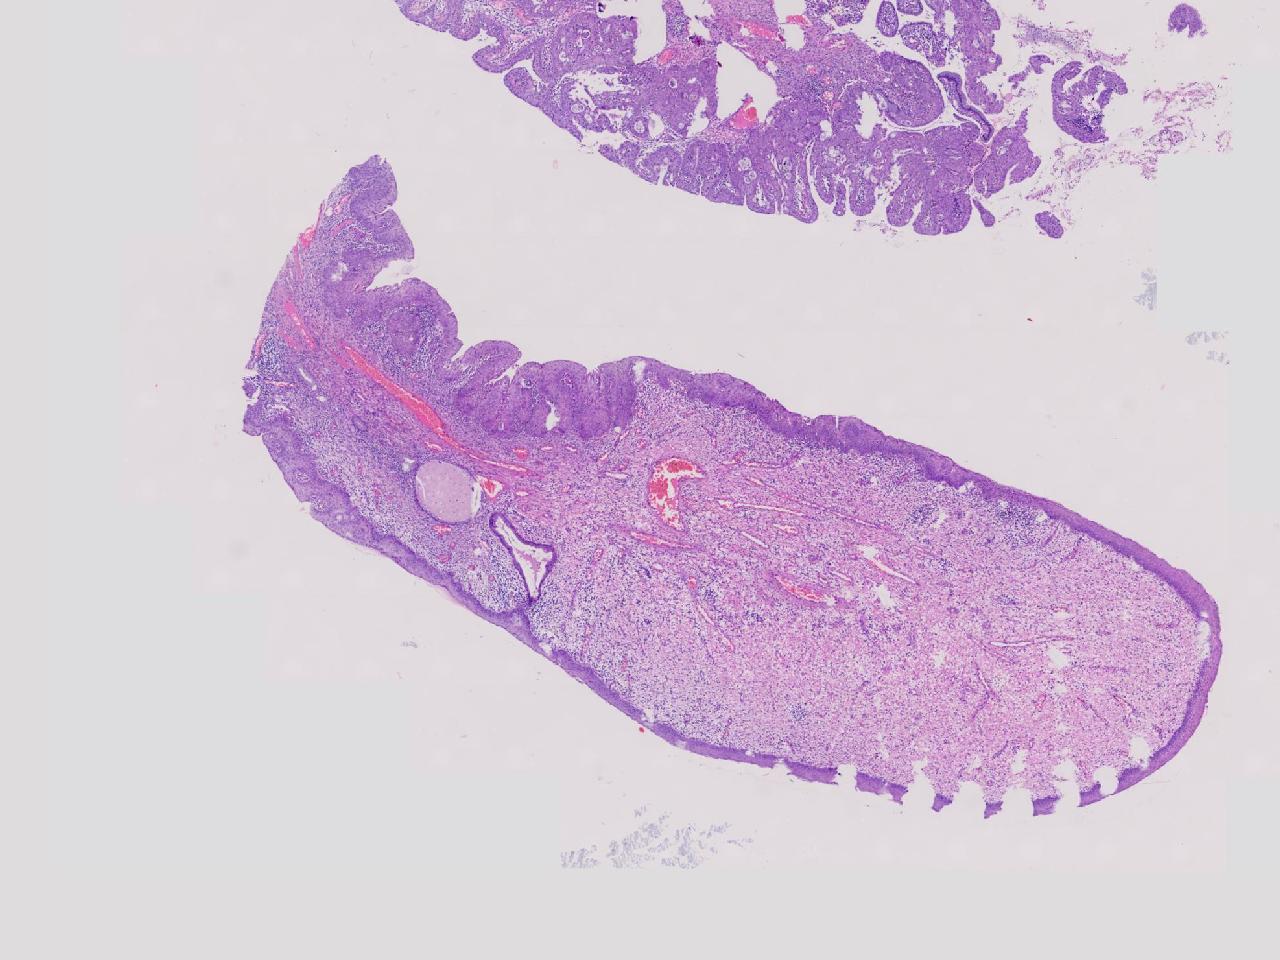

炎? 低级别?

性别年龄42岁临床诊断宫颈赘生物

一般病史女,42岁,妇检时发现宫颈赘生物,大小0.2cmx0.5cm

标本名称管状赘生物

大体所见灰白色不整形软组织2块,一个直径0.3厘米,一个直径0.2厘米。

炎症

低级别诊断需要有个尺子,这个尺子就是“似是而非为非”,这个连似是而非都达不到。

有非典型鳞化,建议HPV检测

慢性宫颈炎伴腺上皮鳞化。